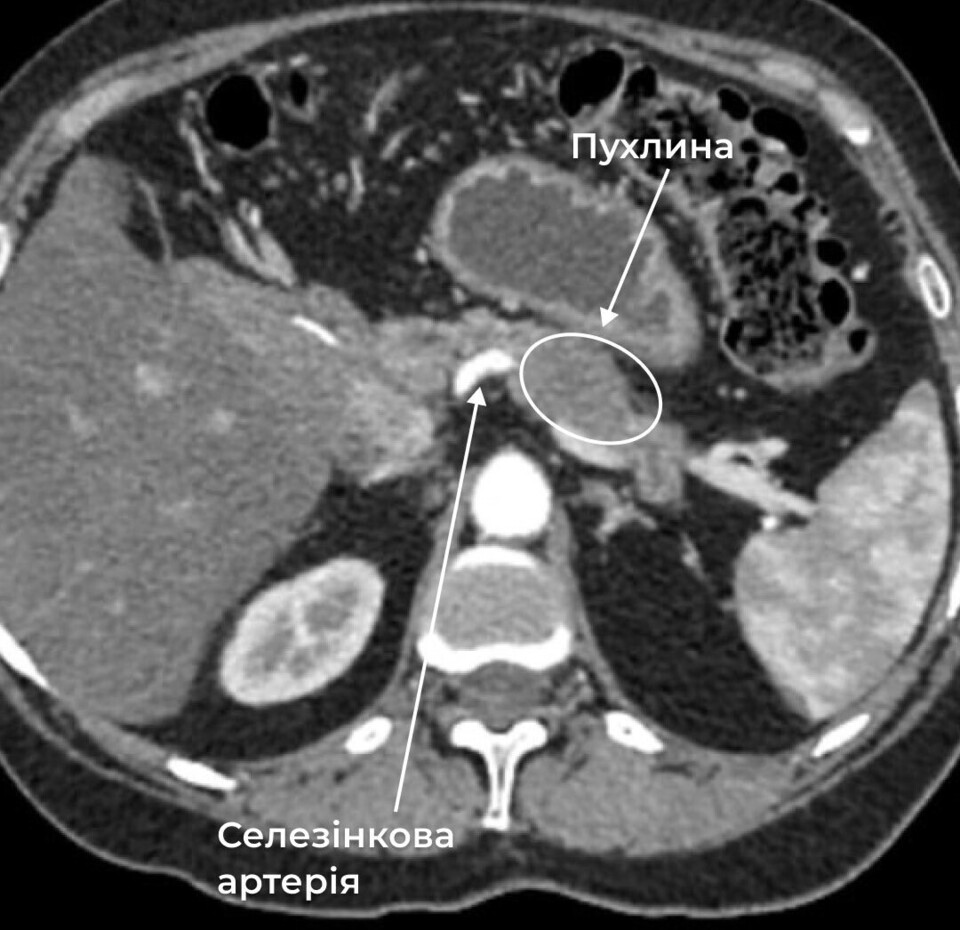

Комп’ютерна томографія підтвердила найгірші побоювання: нову злоякісну пухлину, цього разу — безпосередньо в підшлунковій залозі.

Після трьох місяців хіміотерапії лікарі ухвалили рішення про проведення тотальної панкреатектомії зі спленектомією. Це означало повне видалення підшлункової залози разом із селезінкою. Хірург-онколог Володимир Дорожинський пояснює: